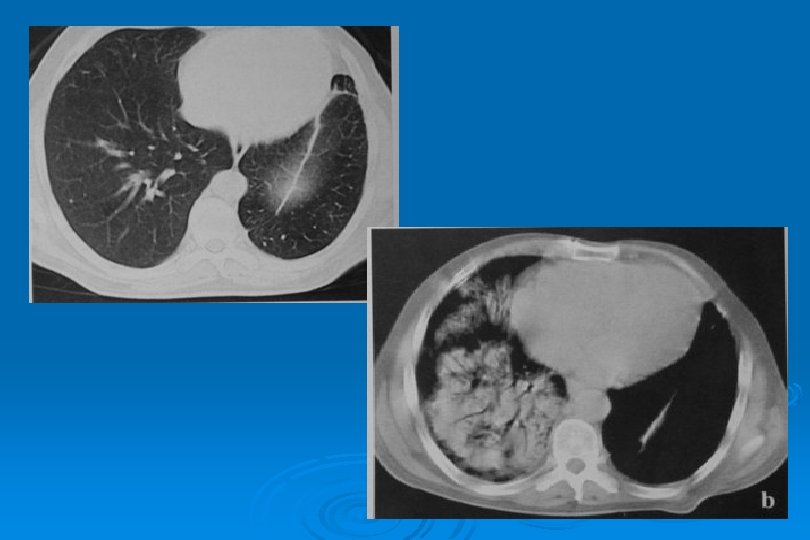

MİKOPLAZMA PNÖMONİSİ Yamalı, segmental veya lobar konsolidasyon veya buzlu cam yoğunluğu Ø İnterstisyumda kalınlaşma Ø Mozaik perfüzyon Ø

M. Pneumoniae Pnömonisi